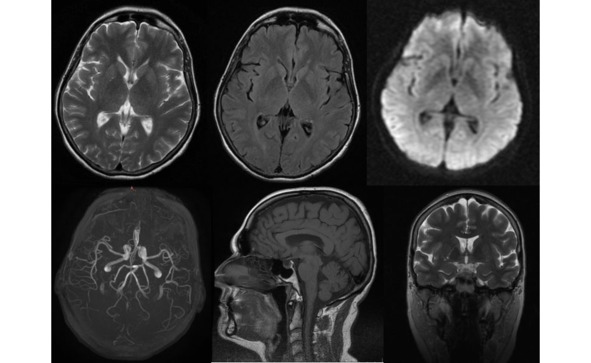

Изменения, выявляемые у пациентов с БП при проведении компьютерной томографии (КТ) и/или МРТ в стандартных режимах являются весьма неспецифичными. Преимущественно по данным нейровизуализации выявляется различной степени выраженности уменьшение объема вещества головного мозга: конвекситальная атрофия корковых отделов мозга, расширение желудочковой системы, которые не являются патогномоничными признаками этой патологии (рис. 13).

Рис. 13. Пример МР-томограмм пациентки 59 лет с БП.

Боковые желудочки мозга не расширены, симметричны (D=S). III-й и IV-й желудочки обычной конфигурации и размеров. Супраселлярная цистерна пролабирует в полость турецкого седла, остальные базальные цистерны не изменены. Субарахноидальные ликворные пространства неравномерно расширены по конвекситальной поверхности в проекции лобных, теменных долей и Сильвиевых щелей. Незначительно расширены периваскулярные пространства Вирхова-Робина по ходу пенетрирующих сосудов. Срединные структуры не смещены. Вертикальный размер гипофиза – до 0,3 см, сохраненная ткань гипофиза имеет обычный МР сигнал.

Более выраженные МР-признаки атрофии отмечаются у пациентов с акинетикоригидной формой заболевания, а также при наличие в клинической картине значительных когнитивных нарушений. Выраженность атрофии нарастает и по мере увеличения тяжести и продолжительности заболевания. Так, при длительности БП до 3 лет атрофия выявляется у трети пациентов, а при длительности свыше 6 лет возрастает более чем в 2 раза и отмечается у 78% пациентов.